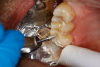

Figure 8A is a radiograph revealing deep root caries previously restored temporarily by a resident at the AEGD Residency Program clinic with glass ionomer utilizing a lateral rather than occlusal approach. After the glass ionomer failed to adhere, another resident again attempted a lateral approach that resulted in the restoration shown in Figure 8B. A third resident had success with an occlusal approach, removing a failed occlusal composite to access the distal  (Figure 9). This attempt was successful both in the preparation of the lesion and in the placement of a dual- cure bulk-fill flowable (Bulk EZ Plus, Zest Dental Solutions; alternatively: HyperFIL®, Parkell; Fill-Up!, Coltene) extruded through a bendable needle (Figure 10). Figure 11 shows the final preparation after tissue removal was accomplished with rotary gingitage; note that this was performed with the rubber dam in place. An air abrasion device (Groman Etchmaster, Groman Dental; alternatively: PrepStart H2O, Zest Dental Solutions; Bioclear Blaster, Bioclear) was used with potassium bicarbonate to remove biofilm prior to acid etching (Figure 12). Phosphoric acid 37% was utilized in a total etch fashion (Fig- ure 13 and Figure 14) for 20 seconds. Figure 15 shows the universal bond (Scotchbond Universal, 3M; alternatively: All-Bond Universal®, BISCO; Prelude One, Danville Materials) with metha- cryloyloxydecyl dihydrogen phosphate (MDP) being scrubbed into the cavity for 20 seconds. After air thinning for 20 seconds, the adhesive was light cured for 40 seconds at 1,200 mw/cm2power density (Figure 16).

Fig 11. Final preparation after gingitage with coarse diamond bur to remove soft tissue from the cavity in tooth No. 2.

Figure 11

Fig 12. Utilizing particle blasting with a microetcher loaded with potassium carbonate to remove biofilm in the cavity and margins.

Figure 12

Fig 13. Total etch with 37% phosphoric acid.

Figure 13

Fig 14. Cavity preparation flooded with phosphoric acid in total etch.

Figure 14